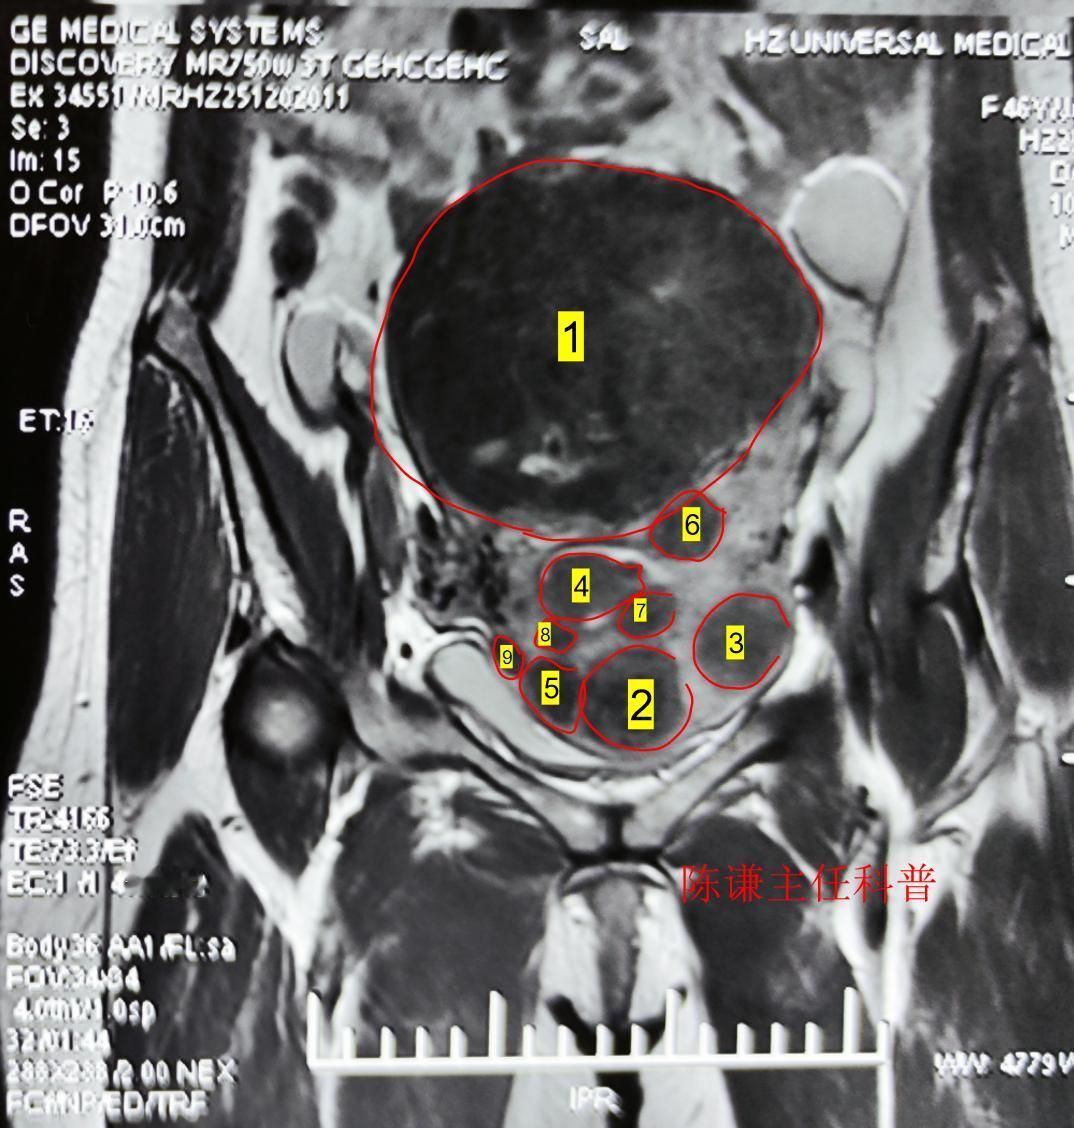

这是我们治疗的一名多发性子宫肌瘤患者,病人大大小小的肌瘤有数十个,对于这样的患者